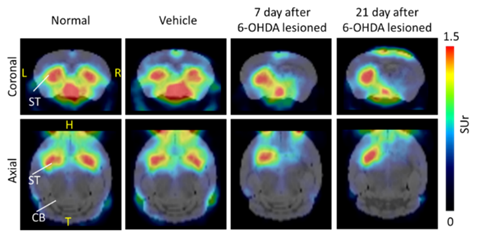

近年來由於醫療技術之進步延長了全球人類平均壽命,然而伴隨了部分神經退化性疾病對年長者後期生活品質的影響,甚至對提供照護之家庭造成相當大的衝擊。阿茲海默氏症及帕金森氏症為最常見之神經退化性疾病,許多不同科學試驗正密集進行,以找出此兩種疾病可能之病理機轉及可行之治療方式。其中,一種結合放射性示蹤劑及造影方式的平台提供了一個可在活體上進行長期病理反應觀察及新藥效益快速評估的可行性。以阿茲海默氏症為例,在西元 2000 年前的研究及資料蒐集絕大部分仰賴過世之患者腦部組織檢體染色所得之結果方可進行分析及判讀;然而,匹茲堡大學的研究團隊於 2001 年發表了第一代使用於放射性正子斷層造影(PET)之試劑―11C-PIB,可於活體中偵測該疾病主要病理特徵「乙型類澱粉斑塊」(圖一),自此可對該類型疾病患者進行活體量測其腦部內該變異蛋白之累積及病變的相關性,進而帶動許多藥廠快速開發針對該疾病治療藥物之篩選,近期已有一兩個藥品已取得美國食品藥物管理局認可,投入阿茲海默氏症的治療。

11C-PIB於正常受試者(上排)及罹患阿茲海默氏症病患(下排)腦部正子斷層造影影像

圖一、11C-PIB於正常受試者(上排)及罹患阿茲海默氏症病患(下排)腦部正子斷層造影影像(1)

1. Ikonomovic, Milos D., et al. "Early AD pathology in a [C-11] PiB-negative case: a PiB-amyloid imaging, biochemical, and immunohistochemical study." Acta neuropathologica 123 (2012): 433-447.